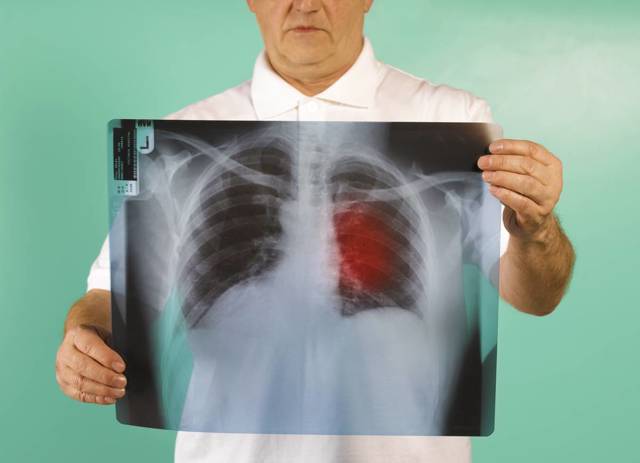

Рентгенографический снимок. Это метод один из самых распространенных при ранней диагностики рака легкого. Хотелось бы отметить, что на снимке можно заметить не четкость, размытость и неоднородность контуров новообразования. Для того чтобы определить данным способом наличие раковой опухоли и поставить правильный диагноз, с момента появления данного заболевания должно пройти около 126 календарных дней.- Магниторезонансная томография. Выявление злокачественной опухоли в тканях легких на ранних стадиях таким способом дает наиболее точную информацию о состоянии плевральной жидкости, состоянии сосудов легочных тканей и степени заражения данным процессом смежных органов.

Базой для констатации наличия новообразования в легких является рентгеновский снимок. Увидеть аномальный участок в легком — задача простая, установить старт того же процесса на первых этапах, довольно сложно.

Рентгенография органов грудной клетки

Основным, чаще всего применяемым исследованием до сих пор остается рентгенография лёгких в двух проекциях. С одной стороны – рентген безопасен и достаточно эффективен: как уже было сказано, в нашей стране в более чем половине случаев рака лёгких диагностика осуществляется во время изучения плановой флюорограммы. С другой — узловое образование в краевой зоне лёгкого (при периферической форме) рентген может выявить лишь, когда оно достигает диаметра 1 см, в корне лёгкого (центральный рак) рентгенограмма «заметит» не ранее, чем оно достигнет диаметра 2 см. Опухоль вырастает их одной-единственной клетки. Для удвоения объема плоскоклеточного рака требуется 120-140 дней, из чего следует, что от момента зарождения онкопатологии до возможности ее обнаружения проходит не менее 10 месяцев.

Мнение о том, что опухоль на снимке имеет округлую форму не совсем верно. Рак лёгких на ранних стадиях (опухоль диаметром до 2 см.) чаще выглядит как звездчатый рубец с нечеткими размытыми контурами. Только по мере роста картина опухоли приобретает округлую или овальную форму.

Также обращают внимание на рентгенологические проявления стеноза (сужения) бронхов, состояние окружающих органов, тканей, лимфатических узлов. Рак лёгких на флюорограмме ничем не отличается от такового на рентгенограмме.

Наиболее распространенным методом диагностирования рака легких выступает рентгеноскопия и флюорография, которую возможно сделать в любой городской больнице.

Рентгеноскопия характеризуется высокой степенью информативности и в 80% случаев позволяет обнаружить легочную онкологию. Лишь в малой доле случаев, рентгеноскопия отображает нормальное состояние легочных тканей при наличии онкологического процесса легочной системы.

При центральной форме ракового образования, на рентгенографии будет отображаться, что в легких присутствует расширенная сеть сосудов, а также имеются замутненные участки. Когда у легочной онкологии периферический характер, картина на рентгеновском изображении будет отображать присутствие четкой тени с неровными краями, от которой к корню легких отходят отростки в виде лент.